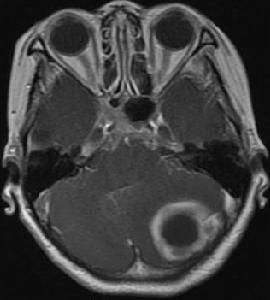

耳源性脑膜炎(otogenic meningitis)是急性或慢性化脓性中耳乳突炎所并发的软脑膜、蛛网膜急性化脓性炎症。[1]